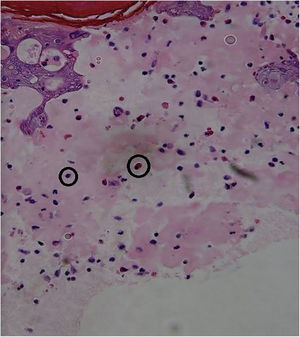

| Skin Biopsy | – | Compatible with viral infection, probable HFMD (Fig. 4) | Compatible with viral infection, probable HFMD |

A skin biopsy is not necessary for an accurate diagnosis, but it is very useful to rule out differential diagnoses. In HFMD histology, intraepidermal blisters with neutrophil content, mononuclear cells, and eosinophilic proteinaceous material are observed. Spongiosis, reticular degeneration of the granular layers and the upper part of the stratum spinosum, keratinocyte mass necrosis, neutrophil exocytosis, and basal-layer hydropic degeneration are also observed. These findings help perform a diagnosis by correlating them with the clinical presentation and the remaining laboratory tests. DNA amplification through RT-PCR is the preferred method for an accurate diagnosis of an atypical disease, but this is only performed at high-tech laboratories and is not available at the present study’s institution.3,5